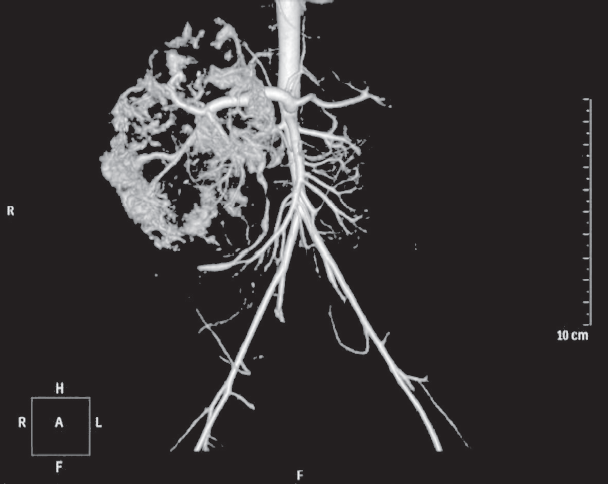

Hemangiomas are the most frequent tumors of childhood age. In the first year of life their prevalence is 10–12%. Among premature children, the prevalence of hemangiomas correlates with the degree of prematurity. Liver hemangiomas are a wide range of benign vascular formations that can acquire both malignant course and capable of spontaneous regression. Small-sized hemangiomas generally do not require specific treatment and proceed asymptomally. Large-sized formations can cause life-threatening conditions such as severe thrombocytopenia with coagulopathy (Kazabah–Merrit syndrome), anaemia, tumor hemorrhage, spontaneous and traumatic tumor breaks, heart failure associated with intra-tumor bypass of blood flow, abdominal compression syndrome, severe hypothyroidism. Diagnosis of this pathology is carried out on the basis of a set of data of medical imaging, laboratory diagnostics and clinical picture. This review presents key points of general classification, the most characteristic diagnostic signs, as well as basic algorithms of treatment of liver hemangiomas in newborns and children of the first year of life. There are also described 2 clinical cases of newborns with giant liver hemangiomas, which were examined and treated in the pathology department of newborns and infants of Perinatal Center of St. Petersburg State Pediatric Medical University with a description of the peculiarities of the course of each of them.